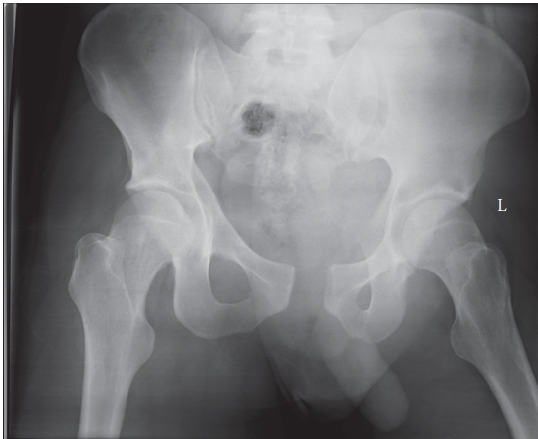

1. Illustration 1 for Pelvic Fracture Case: Test Your Knowledge with this Interactive Module

Clinical Radiograph / Orthopedic Image

What does this radiograph show and how would you classify this injury?

This is an AP radiograph of the pelvis. It shoes an APC II fracture as per the Young and Burgess classification of pelvic fractures. The pubic symphysis has been dis rupted, as well as the sacrotuberous, sacrospinous and anterior SI joint ligaments. The strong posterior SI ligaments appear intact as the left hemipelvis seems to have maintained vertical stability, distinguishing it from an APC III or vertical shear type injury.